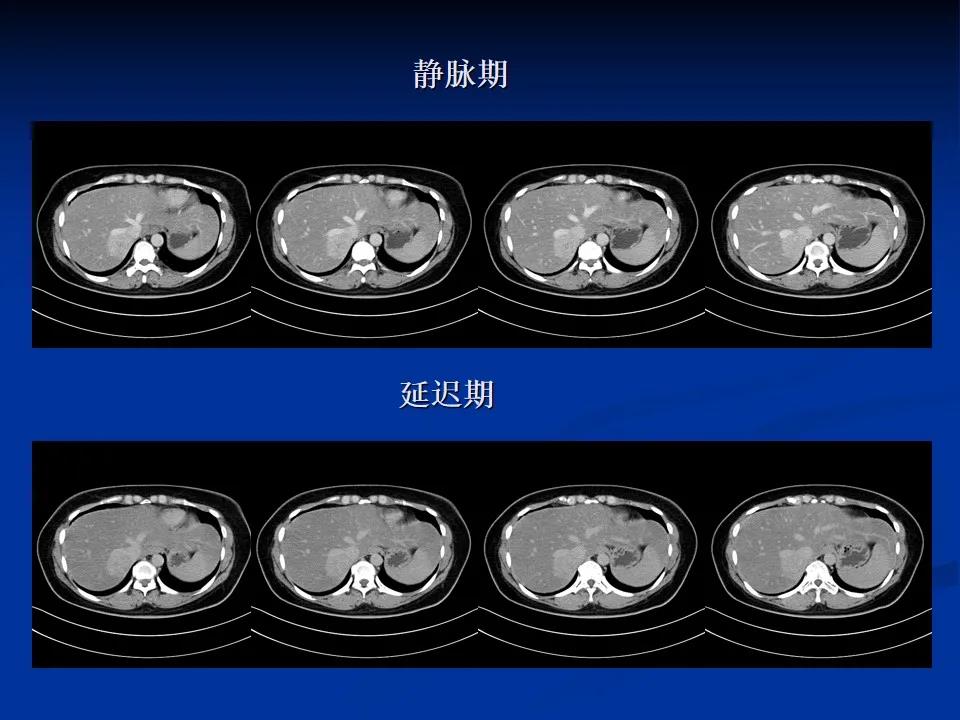

CT动态增强扫描+MRI平扫

诊断意见为肝右叶后上段富血供肿块,倾向于良性,以FNH(肝局灶性结节增生)或肝腺瘤相鉴别,以前者可能大。为进一步明确肿瘤性质及明确下一步诊疗方案,行肝特异性对比剂增强扫描。

扫描后诊断意见为肝右叶后上段富血供肿块(瘤体以含肝正常细胞、纤维组织为主),病灶紧贴肝右静脉、下腔静脉,考虑肝局灶性增生结节(FNH),建议定期复查。